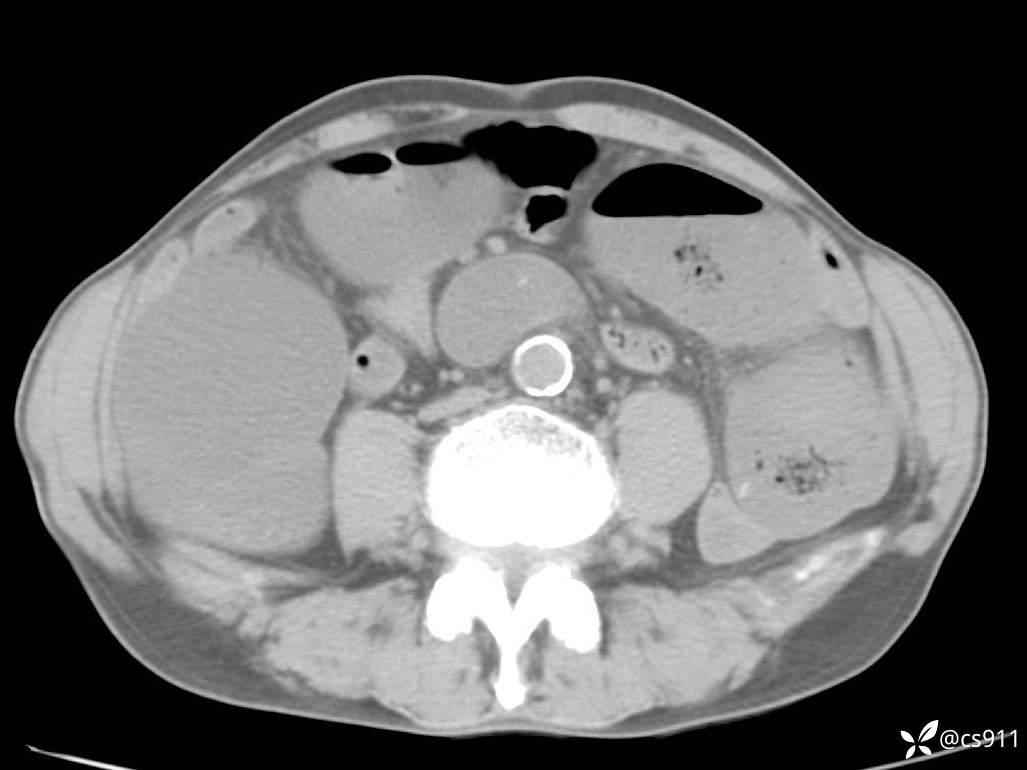

急腹症之急诊CT,原因?答案公布

男,77岁,腹痛、腹胀伴恶心呕吐1天。呕吐胃内容物,非喷射性呕吐,有咖啡色样胃内容物,诉有胃穿孔病史。查体:全腹平,下腹部压痛,全腹无反跳痛,叩诊呈浊音,移动性浊音阴性,肠鸣音减弱,1-2次/分。肛检:直肠未扪及明显肿物,可触及大量粪块。

T 36.6℃ P 80次/分 R 26次/分 BP 100/60mmHg

白细胞(WBC) H 14.55 10e9/L 4-10

中性粒细胞百分率(NEUT%) H 85.7 % 40-75

血淀粉酶(AMY) HH 1859 U/L 35-135

癌胚抗原(CEA) H 27.44 ng/ml 0-5

呕吐物 潜血试验 * 阳性 阴性

患者轮椅入室检查神志清楚, 能配合摆位和呼吸